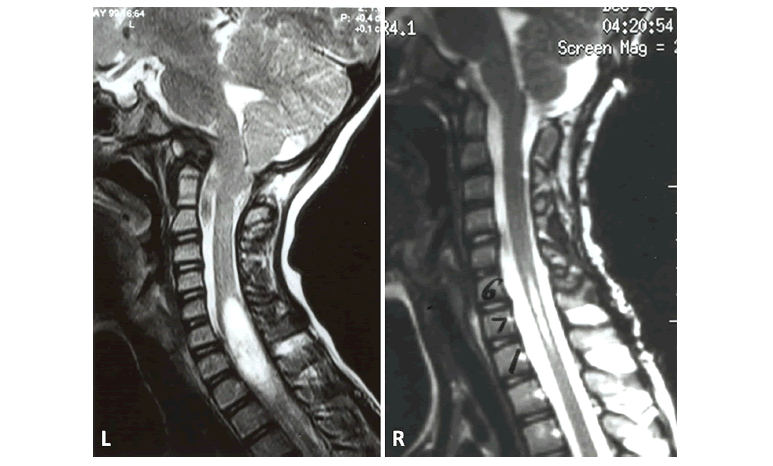

Figure 3: Case #3; A) Awake fiberoptic intubation with “Miami J” collar in place (X). B) Placement of crown halo for intraoperative traction. The head is stabilized during the procedure (chin fixed) and the posterior collar shell is in place. C) Operative photograph of dorsal C1-C2 arthrodesis with screws and rib grafts. D) Postoperative lateral cervical spine radiograph reveals C1 lateral mass screws and C2 pars screws with interscrew rod fixation.

Figure 4: Case #4; A) Coronal T2-W MRI of craniocervical region. Note the O-C1 dislocation with cervicomedullary distortion. B) Anesthetized patient in O-arm CT in traction. C) Composite of axial, coronal and sagittal plane CT in the “O-arm” CT in traction. The rotary dislocation is reduced. D) Postoperative lateral cervical radiograph. There is a completed dorsal occipitocervical fusion.